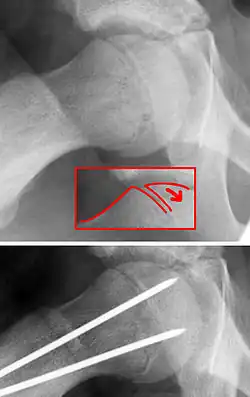

X-ray showing a slipped capital femoral epiphysis, before and after surgical fixation. | |

The disease can be treated with external in-situ pinning or open reduction and pinning. Consultation with an orthopaedic surgeon is necessary to repair this problem. Pinning the unaffected side prophylactically is not recommended for most patients, but may be appropriate if a second SCFE is very likely.[11]

Once SCFE is suspected, the patient should be non-weight bearing and remain on strict bed rest. In severe cases, after enough rest the patient may require physical therapy to regain strength and movement back to the leg. A SCFE is an orthopaedic emergency, as further slippage may result in occlusion of the blood supply and avascular necrosis (risk of 25 percent). Almost all cases require surgery, which usually involves the placement of one or two pins into the femoral head to prevent further slippage.[12] The recommended screw placement is in the center of the epiphysis and perpendicular to the physis.[13] Chances of a slippage occurring in the other hip are 20 percent within 18 months of diagnosis of the first slippage and consequently the opposite unaffected femur may also require pinning.

The risk of reducing this fracture includes the disruption of the blood supply to the bone. It has been shown in the past that attempts to correct the slippage by moving the head back into its correct position can cause the bone to die. Therefore the head of the femur is usually pinned 'as is'. A small incision is made in the outer side of the upper thigh and metal pins are placed through the femoral neck and into the head of the femur. A dressing covers the wound.